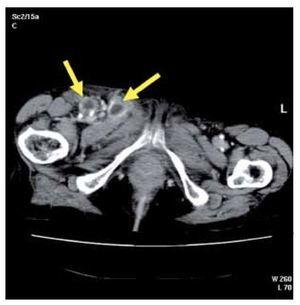

An 82-year-old female was admitted to hospital with seven-day history of right inguinal pain. The patient also complained of fever and malaise. There were no other associated symptoms and she denied a previous trauma. On physical examination she was febrile but other vital signs were normal. The chest exam revealed clear lungs with normal heart sounds and her abdomen was soft with normal bowel sounds. Only mild tenderness in the right flank was present. Her right leg was markedly swollen, indurated and with a descending erythema from her groin and proximal third of the tight to her knee. She had a painful and fluctuant area in her right groin and she also had physical signs of psoas inflammation. Laboratory studies showed leukocytosis with neutrophilia and D-dimer elevation. Deep venous thrombosis was initially suspected, so patient underwent Doppler ultrasonography. As this study did not show any alteration, a computed tomography (CT) was performed to investigate an infectious origin. The CT of the abdomen and pelvis revealed a right iliopsoas abscess affecting obturator (Figure 1) and adductors muscles reaching the distal third of the thigh adjacent to her knee. Multiple inguinal necrotic lymph nodes were also present (Figure 2). As a gastrointestinal infectious focus was suspected a diagnostic laparoscopy was decided, but there were no findings at surgery. Surgical drainage through right groin was made and purulent material was taken for culture. Intravenous empirical antibiotics were also administrated. Further diagnostic methods were made to elucidate the origin of this process when cultures of the purulent fluid yielded Pasteurella multocida. A new anamnesis revealed that the patient had a domestic cat and finally she remembered getting scratched on her right leg a few weeks ago. Detailed physical examination also demonstrated this little scratch, which probably was the primary source of infection. After surgical drainage and antibiotic therapy clinical course remained uneventful.

¿ Figure 2. Multiple inguinal necrotic lymph nodes and groin abscess.